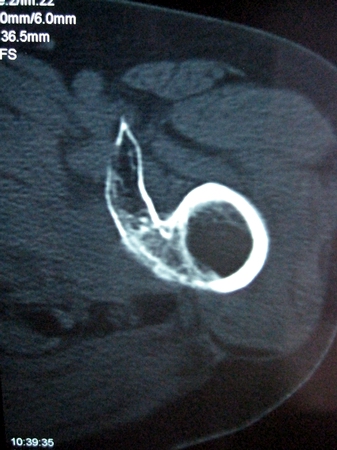

以下是引用lkc8963在2008-12-19 21:19:00的发言:[br]左?右?患侧大转子上移,股骨颈骨质浓杂,髋周见多发条片状骨化影,以小转子为著,多为陈旧性股骨颈骨折后改变并骨化性肌炎.请咨询既往史!